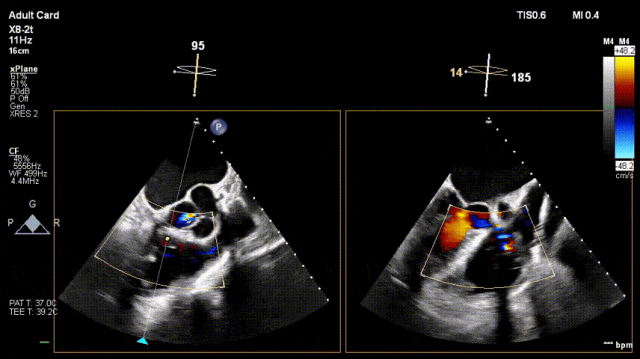

3. After adjusting orientation, position the clamping arms for landing

4. The same procedure is performed for the second clip; the clip morphology is stable under ultrasound